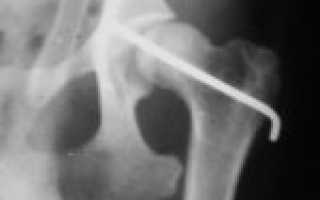

Окончательный диагноз устанавливается на основании рентгенографического исследования (фото 1).

Метод трансартикулярной стабилизации

Суть методики заключается в фиксации тазобедренного сустава в правильном анатомическом положении с помощью металлической спицы, которая проходит через сустав и фиксирует его к дну вертлужной впадины (фото 2). В послеоперационный период животное ограничивают в движении: разрешаются кратковременные прогулки на коротком поводке и содержание в ограниченном пространстве. Через 2-3 недели спицу удаляют, а сустав стабилизируется благодаря образованию околосуставной фиброзной ткани. Функция конечности постепенно восстанавливается.

Вывих головки бедренной кости в 90% случаев происходит в краниодорсальном направлении. При осмотре врач может заметить неестественное положение конечности: животное держит ее в полусогнутом и приведенном к телу состоянии, что приводит к медиальному смещению коленной чашечки. При пальпации выявляется отек и болезненность в области сустава. Ветеринарный врач должен сделать рентгеновский снимок, на котором будет видно несоответствие головки бедренной кости и вертлужной впадины (рис. 1). Стабильность тазобедренного сустава обеспечивается круглой связкой, которая крепит головку бедренной кости к вертлужной впадине. При вывихе происходит ее разрыв, что делает невозможным удержание вправленной головки бедренной кости внутри сустава.

Несмотря на характерные клинические симптомы, для подтверждения диагноза необходимо сделать рентгеновские снимки в латеральной и вентродорсальной проекциях. Это позволит подтвердить диагноз, определить направление вывиха, установить наличие или отсутствие авульсии на месте крепления круглой связки и оценить состояние костей таза, вертлужной впадины, большого вертела бедренной кости и крестцово-подвздошного сустава.